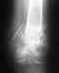

Неправильно срослась ключица (последнее времия становится все болееочевидно - не только на ощупь но и визуально).Ранее не так сильно было заметно.

Перелом произошел примерно 1,5 года назад.Рука не очень силно болела, место перелома не сильно опухло. Показалось что просто ушиб.В общем перетерпел из забыл.За последние пару месяцев ситуация усложнилась:- плечо постоянно ноет,- при круговых движениязх руки плечо "щелкает", иногда возникает онемение в мизинце и безимянном пальце,- над плечем становится заметна небольшая шишка,- на ощупь заметна ступенька между костями примерно в палец высотой.Складывается впечатление, что кость начинает одновременно уходить вглубь в направлении лопатки и вниз.Что посоветуете, куда обратиться?